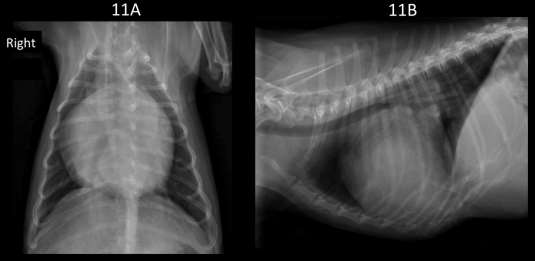

Vertebral Scale System to Measure Canine Heart Size in Radiographs. James Buchanan and Jorg Bücheler. JAVMA January 1995; 206(2): 194-199. Quote: "A method for measuring canine heart size in radiographs was developed on the basis that there is a good correlation between heart size and body length regardless of the conformation of the thorax. The lengths of the long and short axes of the heart of 100 clinically normal dogs were determined with calipers, and the dimensions were scaled against the length of vertebrae dorsal to the heart beginning with T4. The sum of the long and short axes of the heart expressed as vertebral heart size was 9.7 +/- 0.5 vertebrae. The differences between dogs with a wide or deep thorax, males and females, and right or left lateral recumbency were not significant. The caudal vena cava was 0.75 vertebrae +/- 0.13 in comparison to the length of the vertebra over the tracheal bifurcation. ... The major uses of the VHS method are in helping determine whether cardiomegaly exists in dogs with minimal radiographic changes and quantification of the progression of cardiomegaly over time in a glven dog."